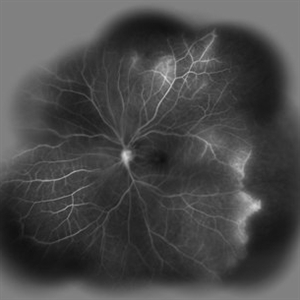

Behcet's Disease Behcet's DiseaseMar 13 2013 by Hamid Ahmadieh, MD Late phase FA of the right eye of a 23-year-old man with retinal vasculitis and branch retinal vein occlusion (BRVO) due to Behcet's disease . Photographer: Solmaz Shahmohammad, Negah Eye Center, Tehran Imaging device: Heidelberg Spectralis Condition/keywords: branch retinal vein occlusion (BRVO), retinal vasculitis

Behcet's Disease Behcet's DiseaseMar 13 2013 by Hamid Ahmadieh, MD Wide field FA of the right eye of a 23-year-old man with retinal vasculitis and branch retinal vein occlusion (BRVO) due to Behcet's disease . Photographer: Solmaz Shahmohammad, Negah Eye Center, Tehran Imaging device: Heidelberg Spectralis Condition/keywords: branch retinal vein occlusion (BRVO), retinal vasculitis